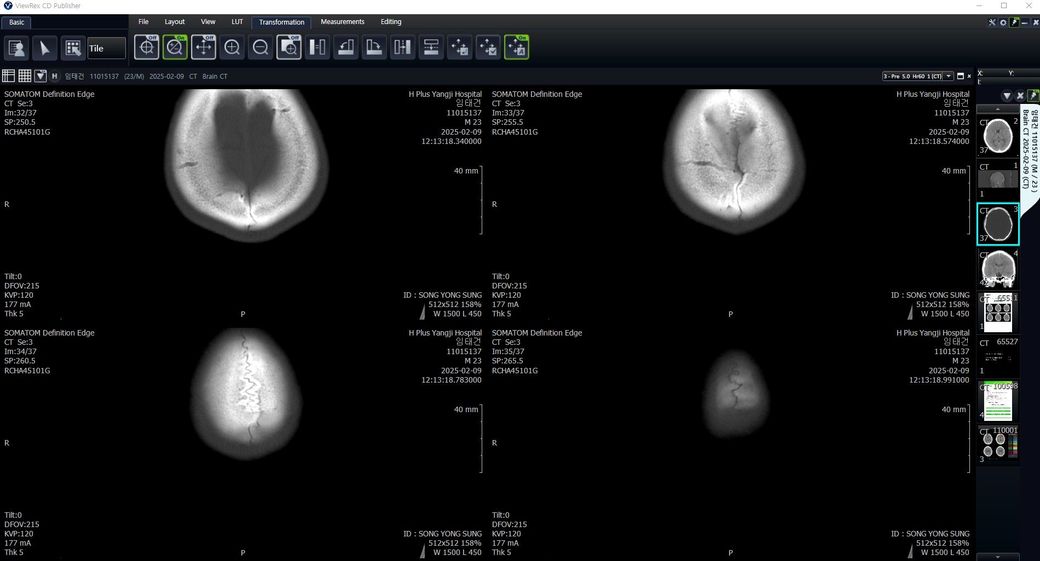

두개골 수술 또는 골절 의심되는 상황인데 엑스레이와 ct사진을 한번 봐주실 수 있나요?

2~3일 정도 기억이 없었는데 그때 머리를 다쳤는지 바로 x-ray와 ct를 찍어봤는데 한번 봐주실 수 있을까요? 진단 목적이 아닌 확인 목적입니다

빨갛게 동그라미 친 곳은 금속물질이 의심도는 부근입니다

• 3번 째 사진